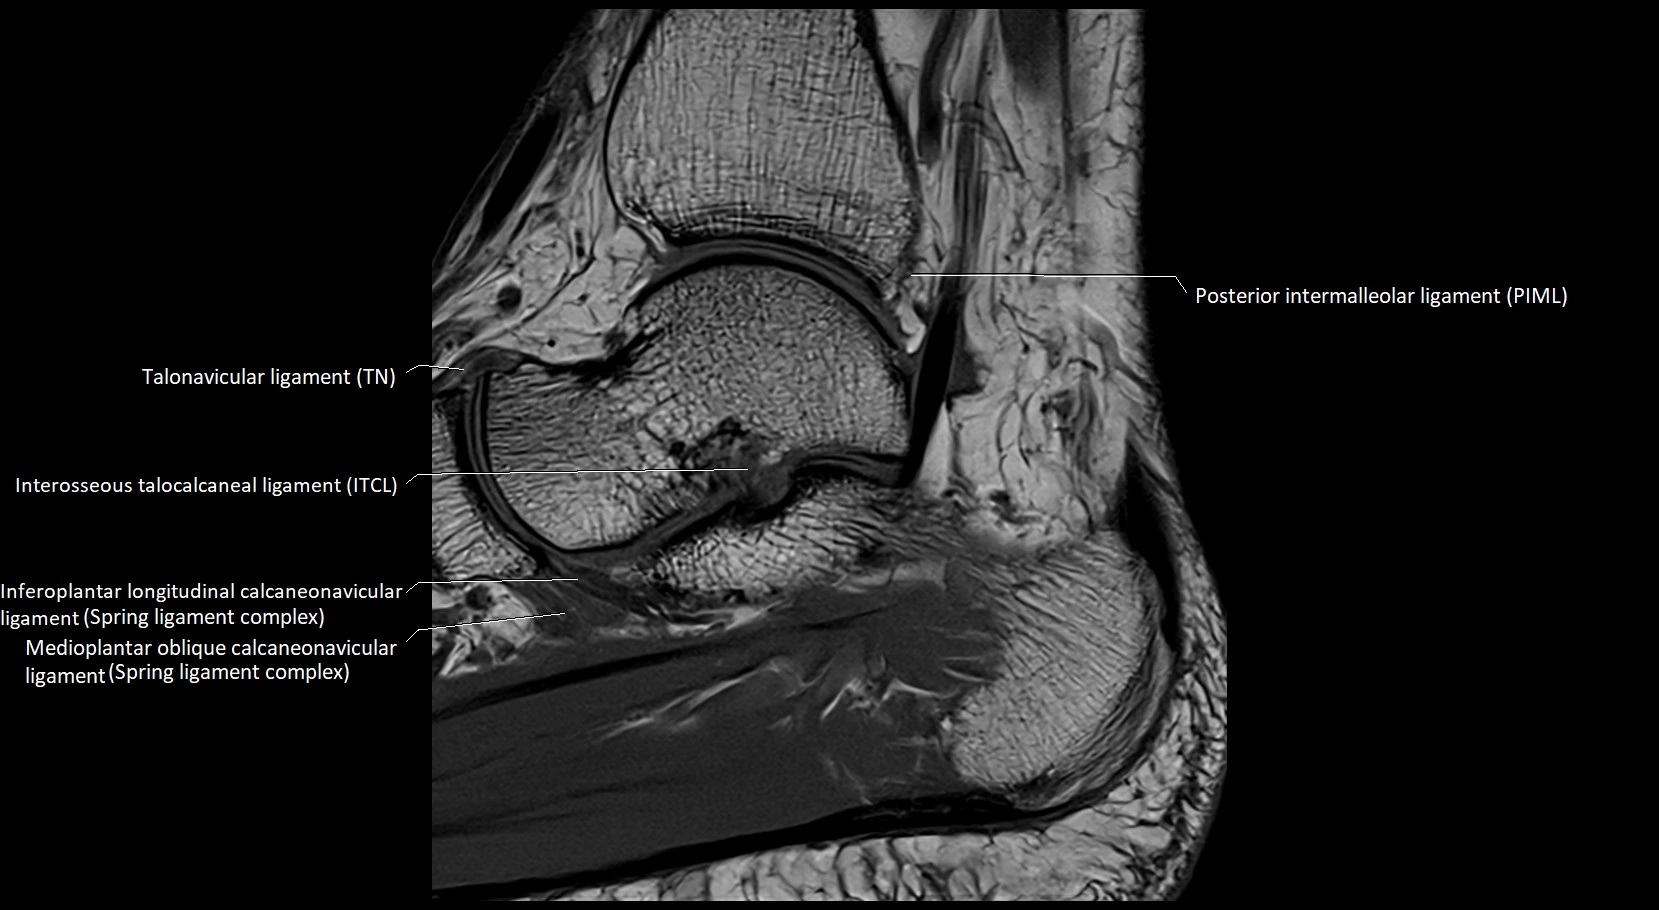

MRI image

image